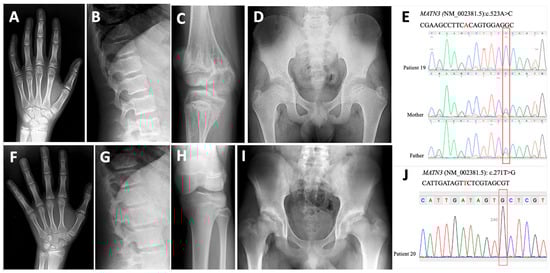

The Chopart amputation is a controversial amputation level and has been described as a relatively non-functional amputation due to the increased risk for stump deformity and subsequent complications. Recent literature has shown that a tibiotalocalcaneal arthrodesis can subjectively increase function in the Chopart amputation. We describe the use of a tibiotalocalcaneal arthrodesis in a 44-year-old diabetic male with a Chopart amputation for the purpose of limb and gait salvage. After 292 days and an uneventful postoperative course, the patient consented to gait analysis. The case allows us to objectively conclude that the tibiotalocalcaneal arthrodesis can quantitatively increase the functionality of the Chopart amputation and, in turn, expand its indication for use within the more functional populations. Full article